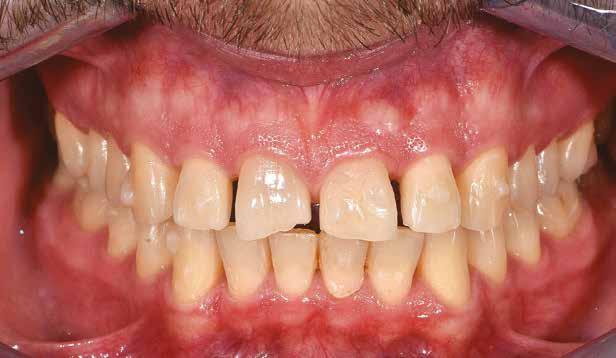

A 26 éves férfi páciens azzal a kéréssel kereste fel a rendelőnket, hogy a frontfogai esztétikusabb megjelenését szeretné elérni. A páciens jó általános egészségi állapottal rendelkezett, nem szenvedett allergiáktól és nem kellett rendszeresen gyógyszereket szednie. A páciens lehetőség szerint kerülte a fogai megmutatását. Rendkívül zavarónak találta a nagymetszői között, a középvonalnak megfelelően látható rést, a fogain látható kopási jeleket, valamint a fogai méretét is túl kicsinek találta. A szájüregi vizsgálat során megállapítottuk, hogy a nagymetsző fogai (11, 21) élharapásban vannak, valamint az alsó fogíven kismértékű torlódást észleltünk. A felső frontfogakon

(13-23) attrícióra utaló jeleket találtunk. A fogak kopása a nagymetszőfogaknak megfelelően volt a legkifejezettebb (1. ábra) . Az előbbiekben említett fogak (11, 21) ezen kívül némileg elfordultak, és jelentősebb méretű diasztéma volt köztük. A páciens Angle I.-osztályú állcsontrelációs helyzettel rendelkezett. A vizsgálat során feltűnt, hogy a páciens csak nagyon óvatosan mert mosolyogni (2. ábra)

A szájüregi vizsgálat során nem találtunk szuvas léziók jelenlétére utaló eltéréseket. A nagymetszőfogakon megfigyelhető jelentős mértékű kopás ellenére nem észleltünk craniomandibuláris diszfunkció jelenlétére utaló jeleket. A vizsgálat befejezését követően a pácienst tájékoztattuk a különböző kezelési lehetőségekről. Az esztétikai megjelenés javítása érdekében először egy alignerekkel végzett fogszabályzó kezelés elvégzését, majd a harapási helyzet optimalizálását követően a felső frontfogai kompozittal történő direkt felépítését vagy héjakkal történő ellátását (pl.: non-prep héjak) javasoltuk (3. és 4. ábra).

A fogazat minimálinvazív módon készített héjakkal történő ellátásához a fogaknak olyan pozícióban kell lenniük, amely lehetővé teszi az esztétikai megjelenés additív eljárások alkalmazása mellett történő optimalizálását.1. ábra: Kiindulási állapot. A felső nagymetszőfogak élharapásban vannak. 2. ábra: Az orthodonciai kezelés megkezdése előtt készített intraorális felvétel. A páciens csak óvatosan mer mosolyogni. 3. és 4. ábra: Digitálisan megtervezett kezelés.